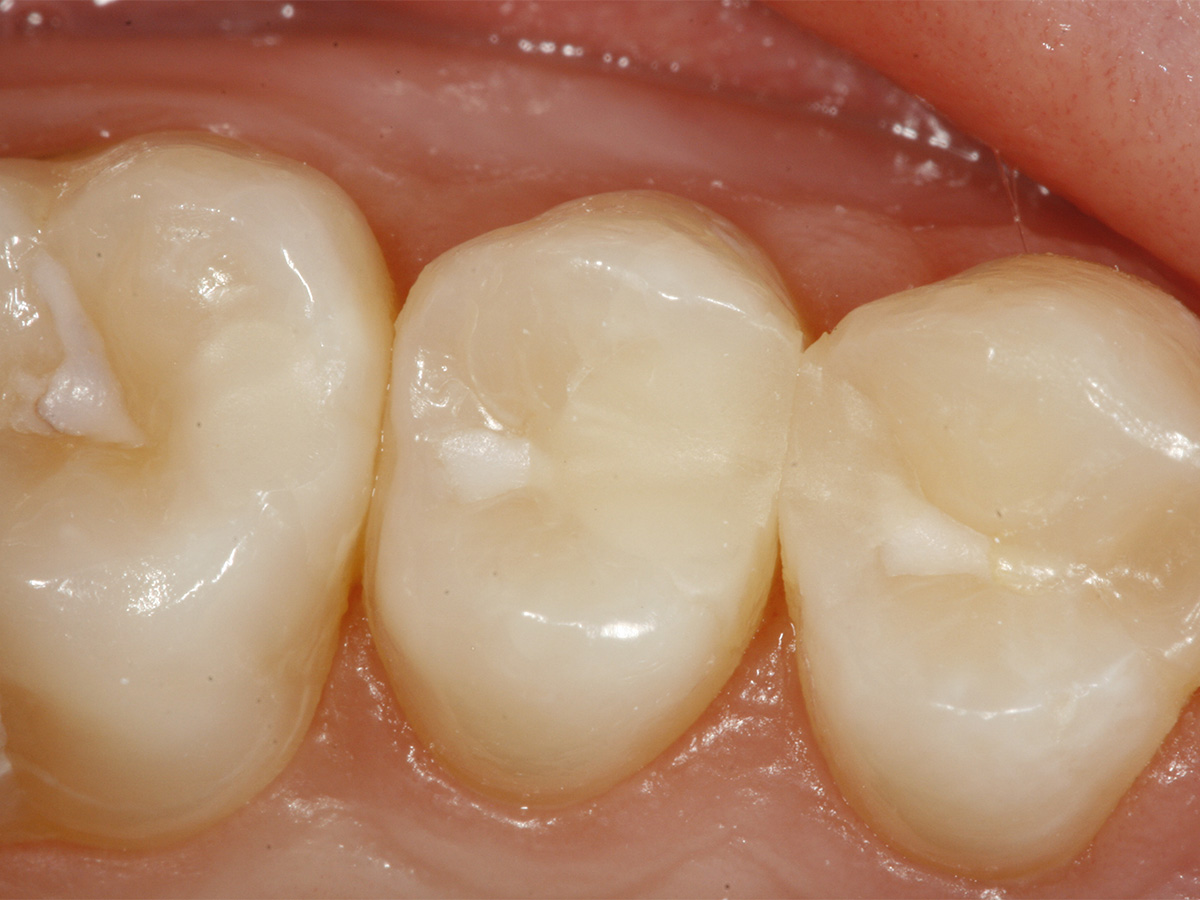

Abbildung 15

Recall 25: Klinisches Bild nach fünf Monaten.